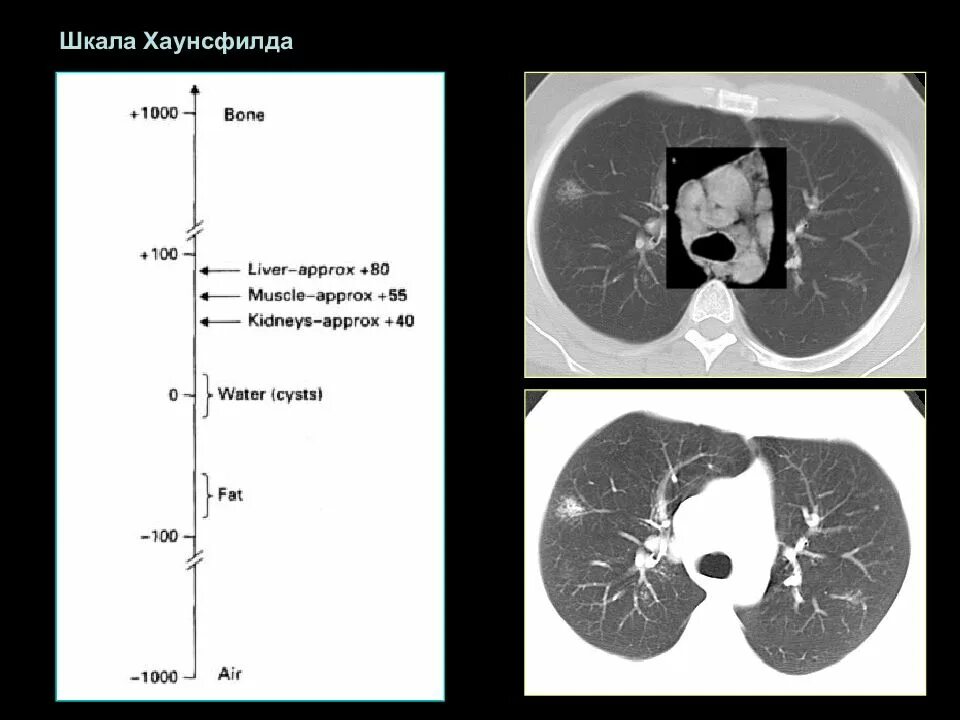

Плотность на кт